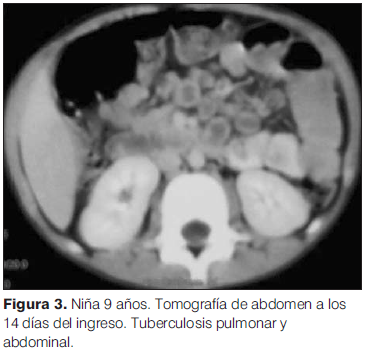

Ante la persistencia del dolor abdominal se solicitó una ecografía que mostró múltiples adenomegalias abdominales de hasta 25 mm de diámetro, que impresionaban corresponder al territorio mesentérico y retroperitoneal medio. Se realizó una tomografía computada (TC) de tórax, abdomen y pelvis, en la que se observó, en el lóbulo inferior izquierdo, una extensa área de consolidación parenquimatosa, con escaso broncograma áereo y varias imágenes hipodensas, con adenomegalias hiliares izquierdas, subcarinales, en el receso pleura-ácigo-esofágico y látero-traqueales derechas altas y bajas (figura 2). Se identificaron múltiples adenomegalias mesentéricas, con realce periférico y centro hipodenso, aspecto compatible con necrosis (figura 3). El resto del estudio no mostró alteraciones.

Dentro de las manifestaciones extrapulmonares de la TBC infantil se destaca en primer lugar, por frecuencia, la afectación de los ganglios linfáticos. En general existe afectación de ganglios amigdalares, cervicales anteriores, submandibulares y supraclaviculares, secundaria a la extensión de una lesión primaria de los campos pulmonares o el abdomen(16). Los ganglios abdominales no son los más frecuentemente comprometidos. Sin embargo, el compromiso ganglionar es la manifestación más frecuente de TBC abdominal, siendo las linfonódulos mesentéricos, gástricos y peripancreáticos los más frecuentemente afectados(17). En la TC con contraste, la evidencia de adenopatías paraaórticas superiores, mesentéricas o suprarrenales con captación de contraste periférico es sugestiva de TBC(18). En el caso de esta paciente se identificaron múltiples adenomegalias mesentéricas que presentaban realce periférico, compatibles con TBC abdominal.

El compromiso ganglionar abdominal clínicamente se manifiesta por dolor de localización difusa(8), como presentaba esta niña desde el inicio de su enfermedad.